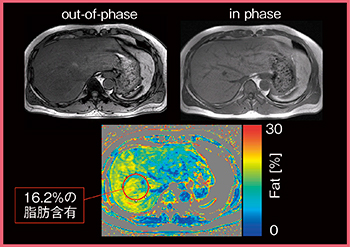

現在,臨床の肝画像診断では,腫瘍の検出能や鑑別だけでなく,原発性肝細胞がんのリスクを把握するために背景肝の評価も求められている。慢性肝障害の原因としては,従来大部分を占めていた肝炎ウイルス感染患者が減少し,近年は非アルコール性脂肪性肝炎患者が増加してきている。これに伴い,背景肝の評価では,肝機能と肝臓への脂肪沈着に重点が置かれるようになっている。

脂肪沈着のMRIによる評価は,out-of-phaseとin phaseを撮像して定性的に判断する方法が一般的に行われているが,病理学的には5%以上の脂肪沈着を脂肪肝と診断するため,わずかな脂肪沈着を画像で定量的に評価することが臨床的に求められている。そこで現在,脂肪を定量評価するfat fraction map(W.I.P.)という撮像・解析方法を日立とともに開発している(図6)。fat fraction mapでは,ROIを設定した部分の脂肪含有率を%で表示することができ,わずかな脂肪沈着にも言及できる可能性があるほか,脂肪性肝疾患の治療効果の判断基準の一つにもなりうると考えている。

図6 fat fraction map(W.I.P.)